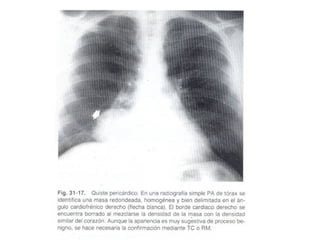

MASAS PERICARDICAS Y PARACARDIACAS